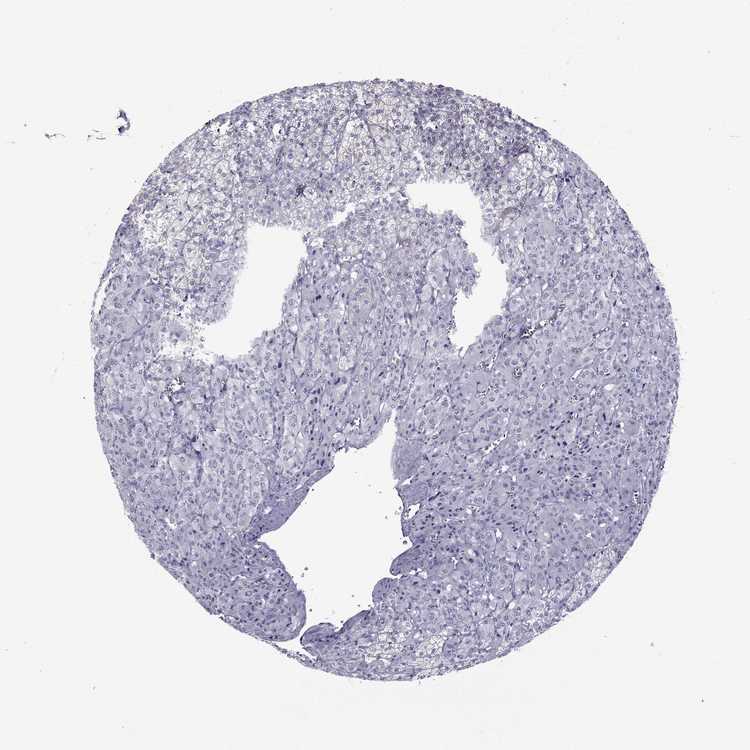

ADRENAL GLAND - Antibody stainingi

Antibody staining in the annotated cell types in the current human tissue is reported as not detected, low, medium, or high, based on conventional immunohistochemistry profiling in selected tissues. This score is based on the combination of the staining intensity and fraction of stained cells.

Each image is clickable and will lead to virtual microscopy that enables deeper exploration of all samples and also displays staining intensity scores, fraction scores and subcellular localization as well as patient and tissue information for each sample.

Antibody HPA074762Antibody CAB075684

Glandular cells Not detectedNot detected